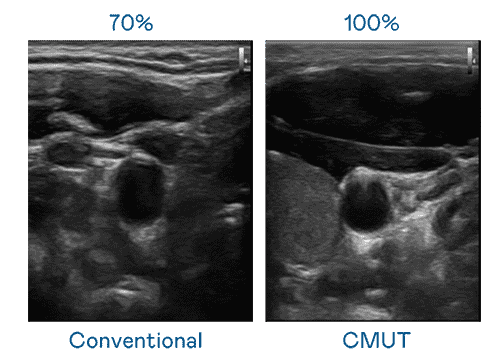

CMUT 技术是一种用电容式微机电元件来产生超音波讯号的技术。。。与传统 PZT 压电式技术相比,,,,CMUT 频宽增加 30%,,更宽频的超音波讯号让影像解析度大幅提升,,是实现高影像品质医疗超音波扫描、、、、促进精准医疗发展的关键技术。。

大频宽带来超清晰影像

超音波影像的解析度高低,,,首先取决于探头能发出的讯号频宽。。918.COM CMUT 可提供高清晰的超音波讯号,,提供高频宽、、高灵敏度、、、、影像纹理细节更高的超音波影像,,,协助医护人员缩短影像判读时间及利用精准的医疗影像进行诊断。。。